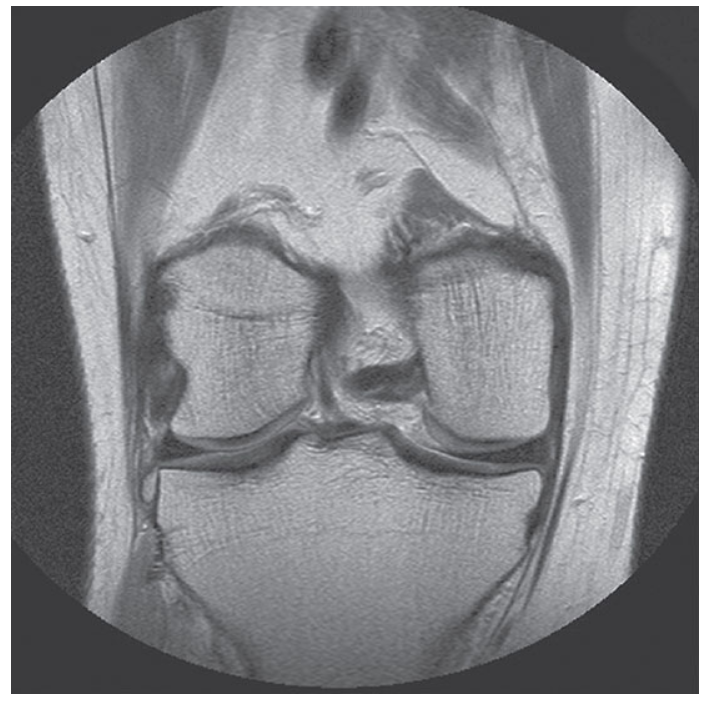

What does this image show?

Coronal TSE PD-weighted image of a knee